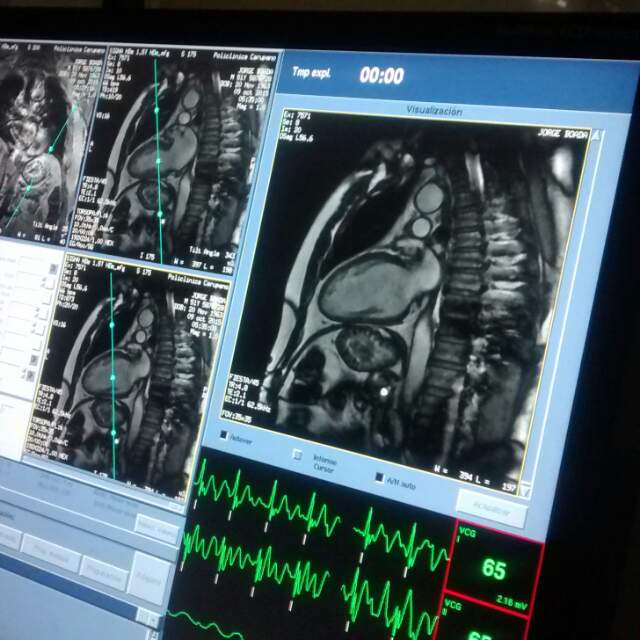

Cardioresonancia o Resonancia del Corazón

Imagen cedida por el Dr. Joel Moreno, (Edo. Sucre Venezuela)

La resonancia magnética cardiaca o

cardiorresonancia es

una técnica de imagen inocua que permite estudiar el corazón, sus órganos

adyacentes y la arteria aorta con una gran nitidez. La máquina de resonancia es

contrario que el escáner o TAC). Permite ver con una gran definición las

aurículas y los ventrículos, siendo posible realizar un estudio exacto de su

anatomía y funcionamiento. De hecho, se considera que es la mejor técnica para

estudiar si el ventrículo se encuentra dilatado y cómo de fuerte se contrae.